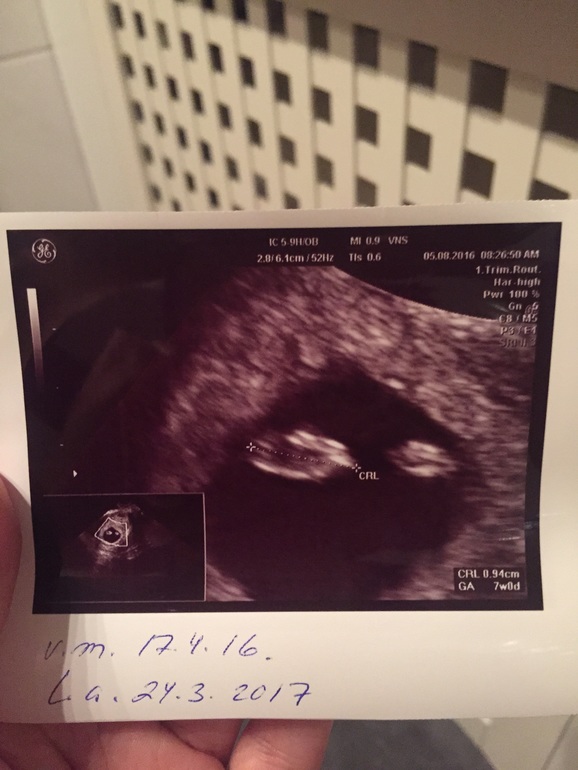

Первое УЗИ

УЗИ, КТГ, доплерСходили мы на первое УЗИ , которое я так боялась :) Все хорошо , все на месте сердцебиение есть:) срок 7+0 ПНД 24.3.2017 Спасибо тебе Господи!!!

Это у вас двойня? Два ПЯ.